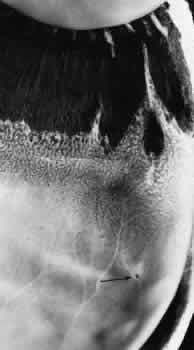

The anterior edge of the peripheral retina is theora serrata, an irregularly scalloped border; the irregularities are more pronounced nasally than temporally and have extreme individual variations in contour (Fig. 5). Dentate or toothlike processes extend anteriorly from the main contour of this bor-der, and bays or indentations extend posteriorly from the main contour of the ora serrata. At theora serrata, those projections of the retina toward the vitreous body are termed meridional folds. There is a concentration of dentate processes, ora bays, and meridional folds in the superior nasal quadrant and a progressive decrease in these morphologic features in the inferior nasal, superior temporal, and inferior temporal quadrants (Figs. 6 and 7). Although individual variations in ora serrata contour may be extreme, studies of adult human eyes demonstrate that both of a patient's eyes are remarkably similar and that statistically, the “average” ora serrata has 16 dentate processes, 1 large or giant dentate process, 10 ora bays, and 1 double ora bay.1,2

Fig. 5. Composite scale drawing depicts peripheral retina, ora serrata, ciliary body, and lens as viewed from posterior aspect. Ora serrata have more dentate processes and ora bays in the nasal quadrants than in the temporal quadrants.

Fig. 6. Peripheral fundus showing preequatorial retina, ora serrata, and inner surface of ciliary body (smooth portion, pars plana; portion with ciliary processes, pars plicata). Ora serrata in this nasal sector shows largely short dentate processes that are typical; that is, they align with valleys between ciliary processes. On right, a giant dentate process is atypical; that is, it aligns with a ciliary process. Aligned with and posterior to the atypical dentate process is a focus of retinal thinning (peripheral retinal excavation). (× 14.)